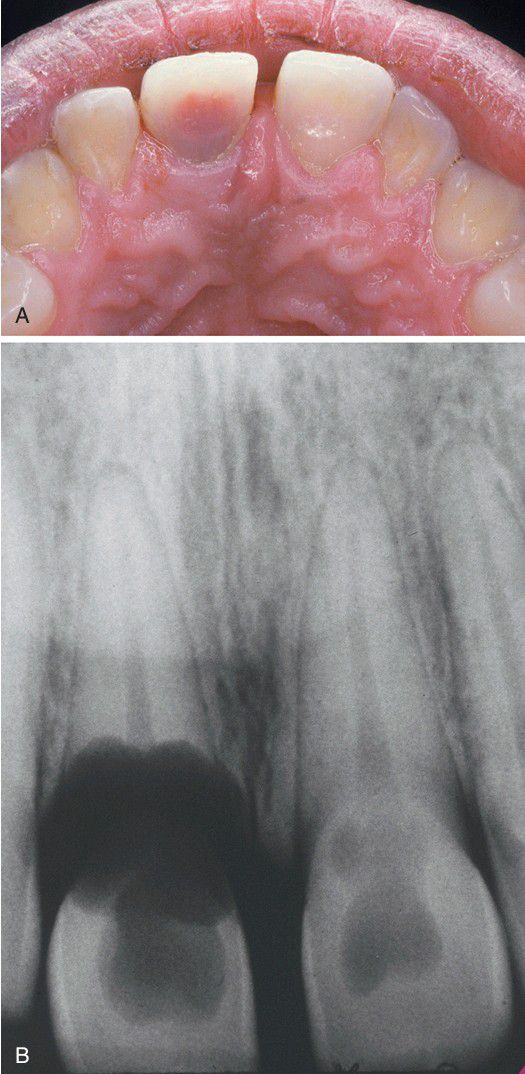

Internal resorption

A. Pink discoloration of the maxillary central incisor. B, Radiograph of same patient showing extensive resorption of both maxillary central incisors.